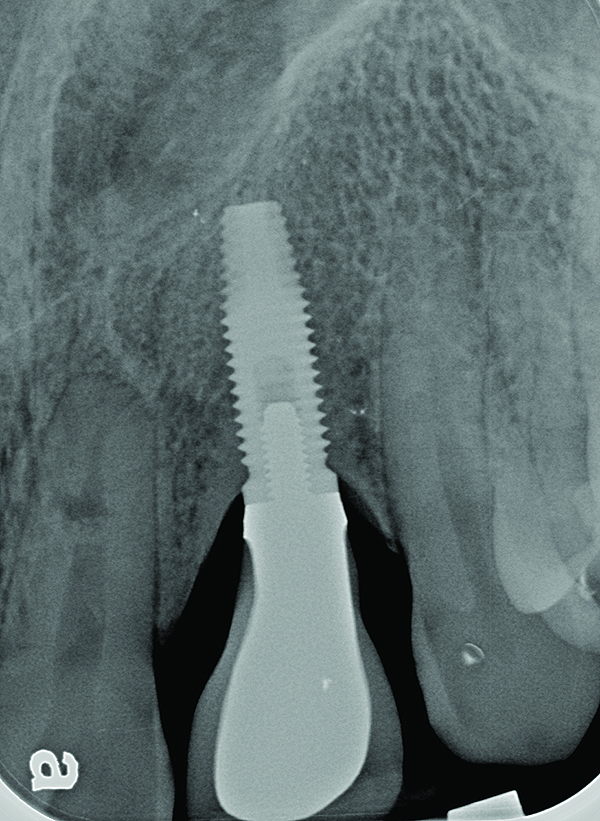

Fig 2. Radiograph of this same area. Note that there is no indication of bone loss and a long abutment collar. Hence, the diagnosis of peri-implant mucositis is given.

Figure 2